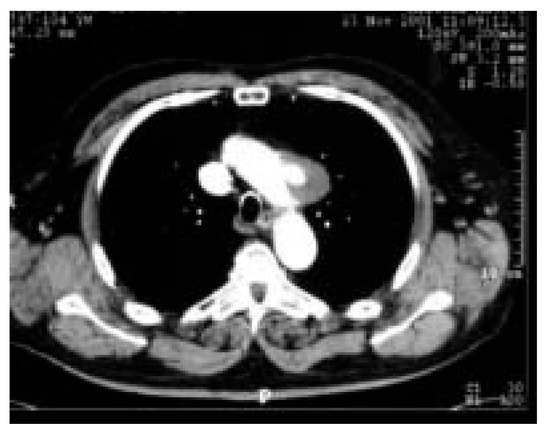

Une patiente de 31 ans souffrant d’une cardiopathie congénitale consulte car elle souhaite une grossesse [...]